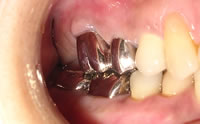

治療後

治療後治療後の状態